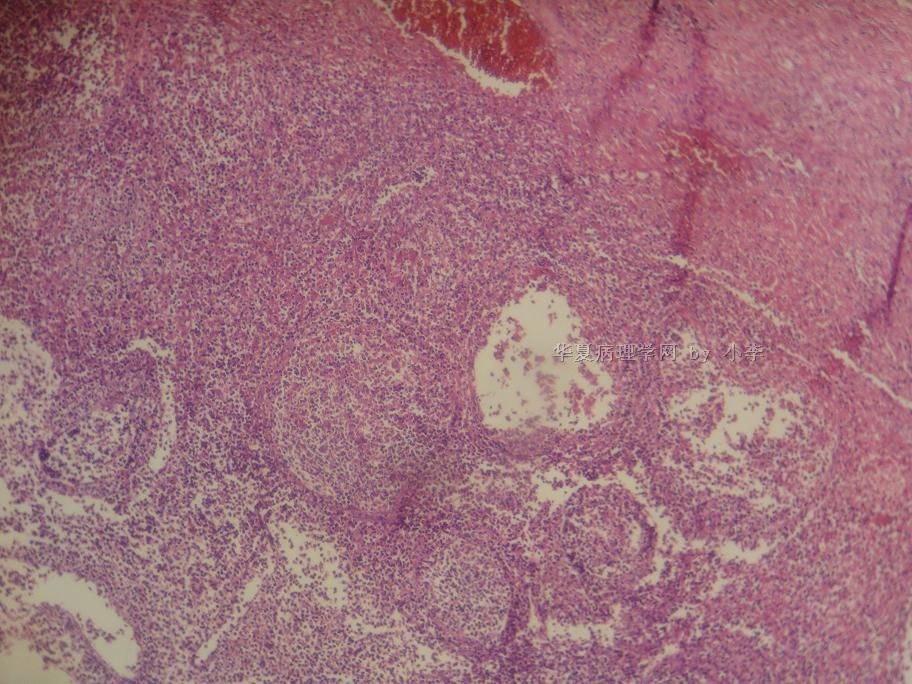

睾丸炎?

姓    名: ××× 性别:  男 年龄: 46岁

• 睾丸炎?图3

图3

首先考虑精子肉芽肿

慢性肉芽肿性炎

肉芽肿性睾丸炎

精子肉芽肿